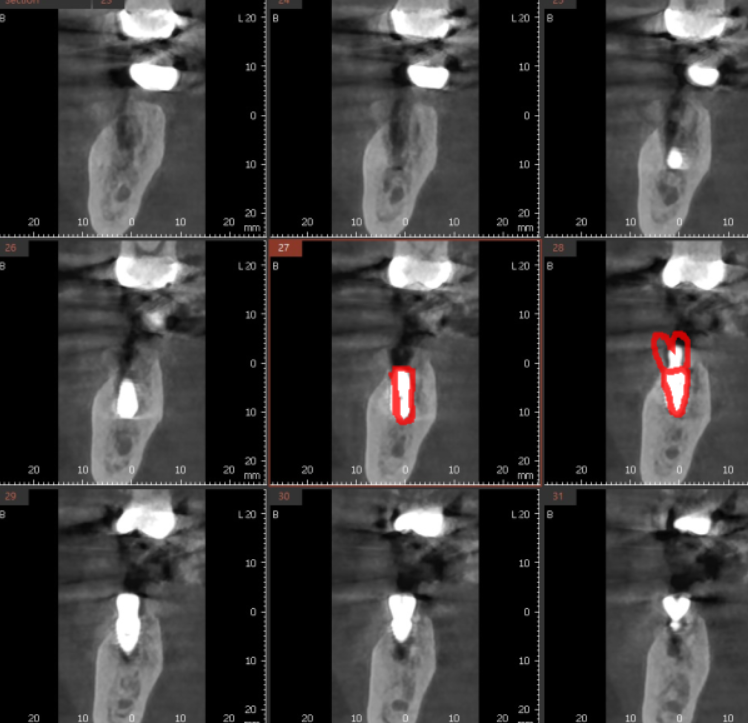

ct를 찍어 얼마나 잇몸뼈가 녹았는지

상태를 보았는데요.

하얗게 차 있어야할 부위가

까맣네요.

염증 지독한 것이

뿌리 모양까지 변화시켰네요.

이전 사진에 비하여 약간 짧아진 게

뿌리까지 흡수되었습니다.

ct 상에서 임플란트 주변으로 잇몸뼈가 잘 찬 것을 확인후

머리를 만들어 주었어요